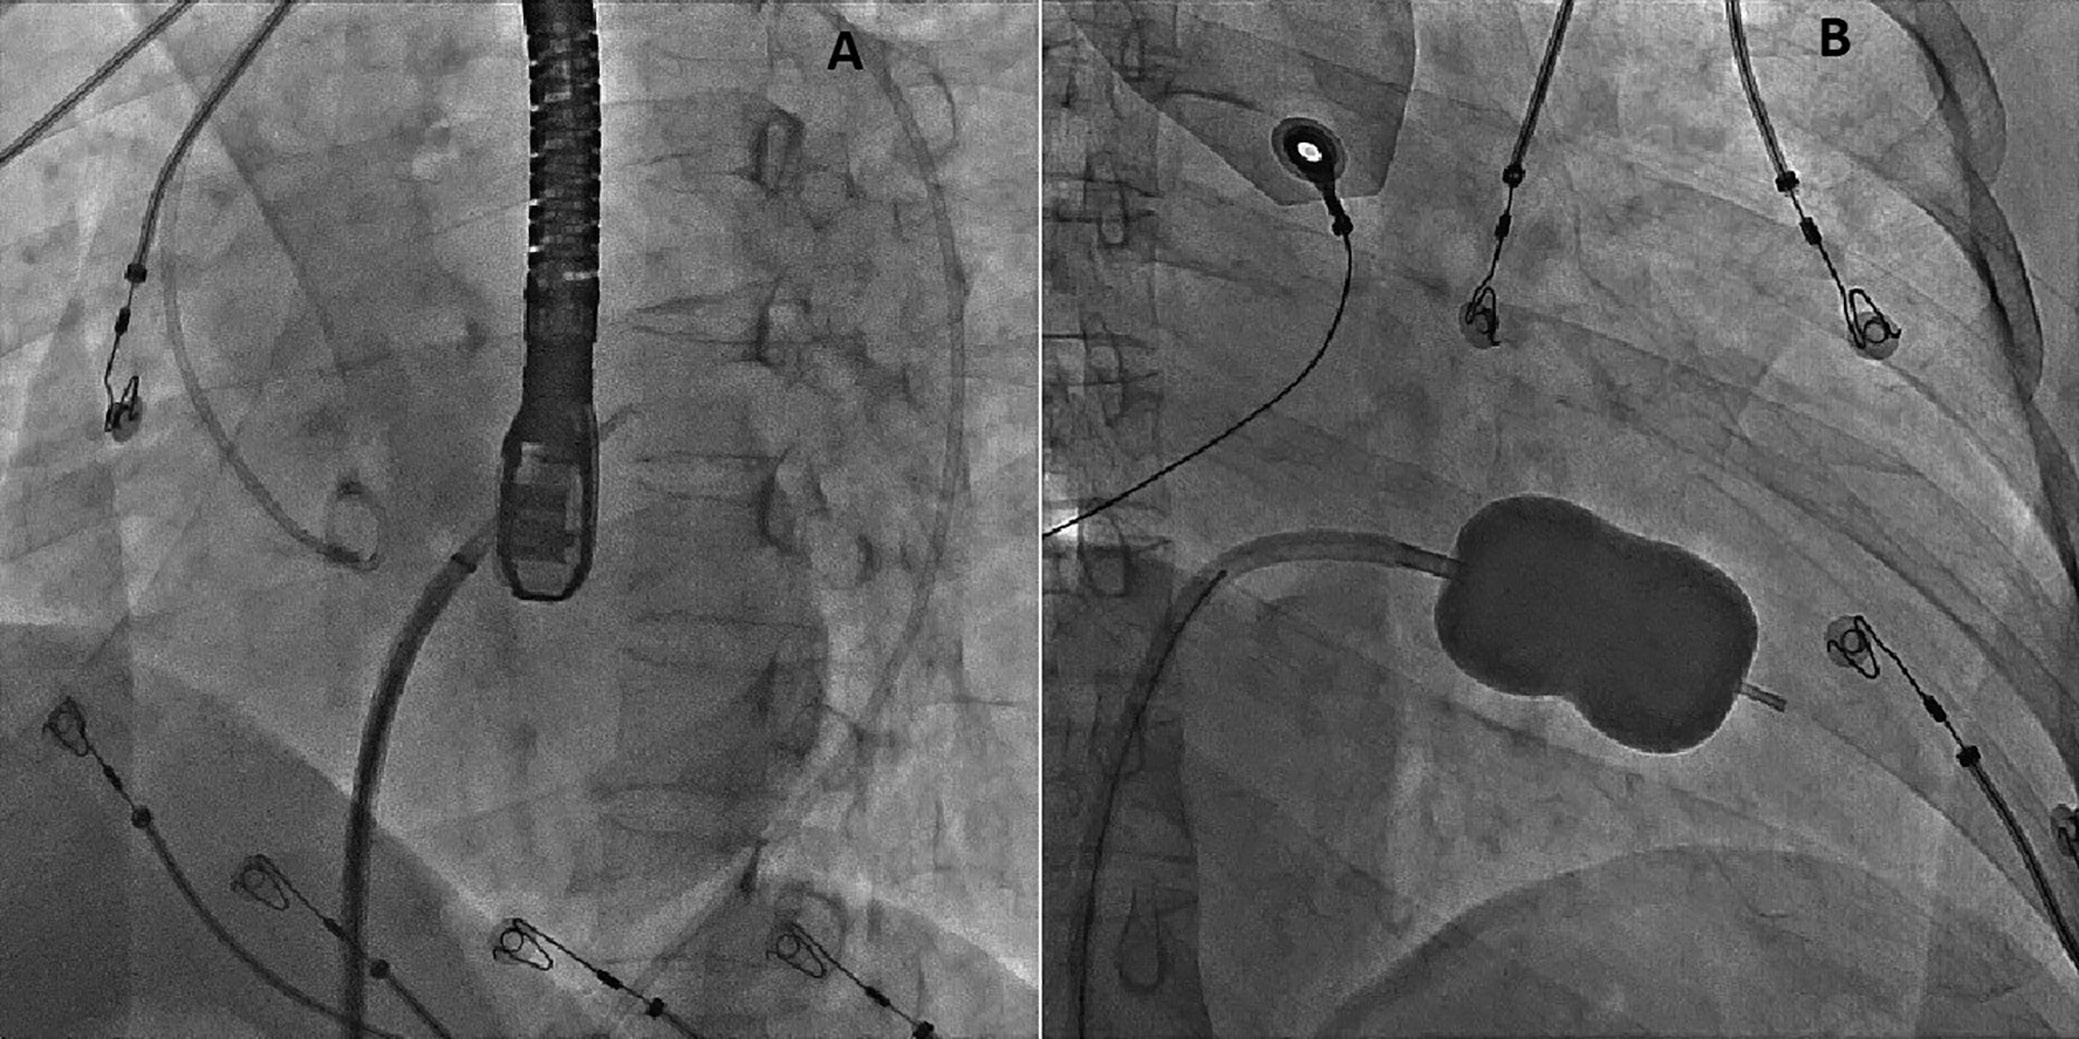

On the day of the procedure, the first balloon mitral valvotomy was performed from a right femoral approach using a 23–26 mm Accura balloon (Vascular Concepts) after transeptal access using an 8 Fr SL-1 sheath and a BRK-0 needle (St Jude Medical). A transeptal puncture was performed after proper needle tip position was confirmed by fluoroscopy (right anterior oblique, left anterior oblique and 90° lateral views) and transoesophageal echocardiography (bicaval and short axis views; Figure 3A). The mean left atrial pressure prior to the valvotomy was 31 mmHg. The balloon was inflated to 26 mm in the right anterior oblique 20° position under fluoroscopy (Figure 3B) because the patient was 160 cm tall. The mitral valve area increased to 2.2 cm2 without any additional mitral regurgitation, and the mean left atrial pressure decreased to 12 mmHg without any mitral valve gradient. Immediate transthoracic echocardiography showed that the mitral valve gradient had decreased to 7/2 mmHg with negligible mitral regurgitation.

electrophysiological study and for possible radiofrequency ablation (Figure 3C). The electrophysiologist proceeded with the ablation plan.

Figure 3: Transsepetal Puncture for Balloon Mitral Valvotomy and Electrophysiology Study in One Go A: Septal puncture using fluoroscopy and transesophageal echocardiography guidance. B: A 23–26 mm Accura balloon was inflated to 26 mm in the right anterior oblique view. Electrophysiological study using one quadripolar catheter for right ventricle pacing and one decapolar catheter in the coronary sinus.